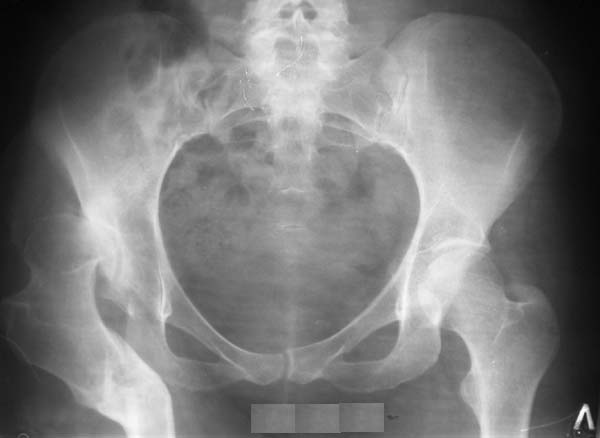

Уважаемые коллеги!Женщина, 35 летВ прошлом по поводу врожденного вывиха бедра перенесла операцию остеотомии по Шанцу

с удлинением правой ноги за счет бедра на уровне диафиза. В последнее время прогрессируют боли в правом тазобедренном суставе, порочное положение правой ноги, затруднена ходьба.Вопросы:1) Целесообразно ли эндопротезирование правого тазобедренного сустава?2) Целесообразный ли следующие действия: канал бедренной кости предполагаем вскрыть для введения ножки протеза на высоте угловой деформации, предполагаем низведение большого вертела с мышцами; протез будет подобран индивидуально, предполагается умеренная версия?В приложении рентгенограммы и трехмерная КТ.В цветном и более качественном варианте КТ размещена здесь

1. Операция (эндопротезирование) показана.

2. К сожалению, техника операции, представленная коллегами из Москвы здесь не получится, т.к. остеотомия бедренной кости была выполнена достаточно низко (по отношению к области сустава). На мой взгляд, целесообразно выполнить остеотомию на высоте деформации с основанием клина кнутри (что бы не было дефекта кости)и ввести понопокрытую ножку с проксимальной и дистальной фиксацией (по типу AML, ее длина 180 мм, при необходимости можно и 200 мм, надо рассчитать). Стабильность ножки будет обеспечена дистальной ее фиксацией, если будут сомнения относительно прочности фиксации короткого проксимального фрагмента, то линию остеотомии можно перекрыть кортикальными аллографтами.